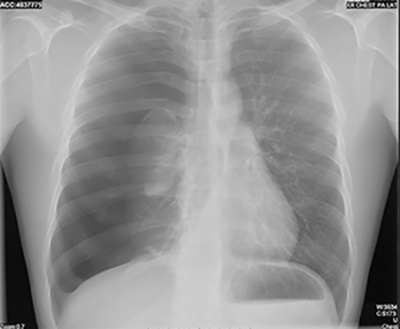

Dyspnea and Back Pain in a 24-yr-old Man

Which of the following is the correct interpretation of this chest x-ray?

The mass is really the collapsed right lung.